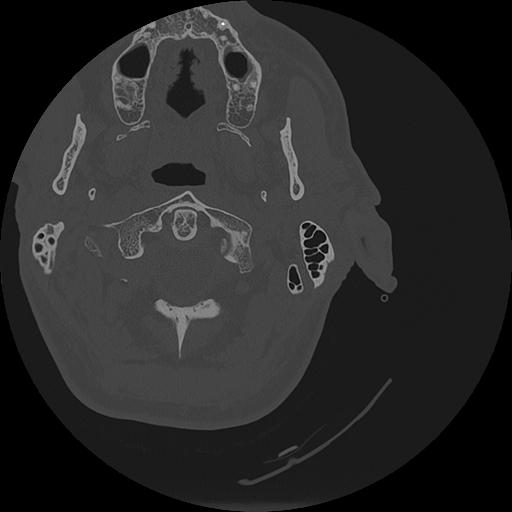

7 HUESO,,Vol,0.5,HUESO,,